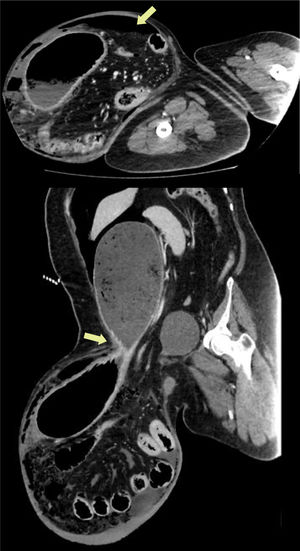

CT scan revealed intestinal loops and part of the stomach within the hernia sac, as well as perforation of the hollow viscus (Fig. 1).